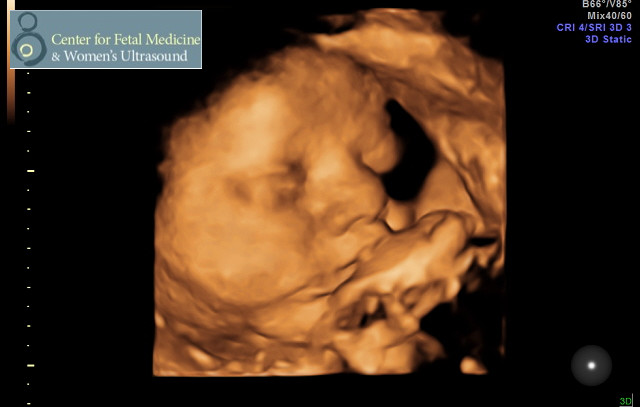

That said, it’s been a lot harder to balance things being pregnant AND having another child who’s doing amazing things. I know I’ve shared the morning sickness leading up to week 15, some ultrasound photos, the gestational diabetes fun (which is still fun, by the way), but this pregnancy is SO different, it’s hard to believe I’m the same person (wait, maybe that’s it?!) OK, maybe not.

Best news is that Ella is right on track for NORMAL weight based on measurements. PHEW.